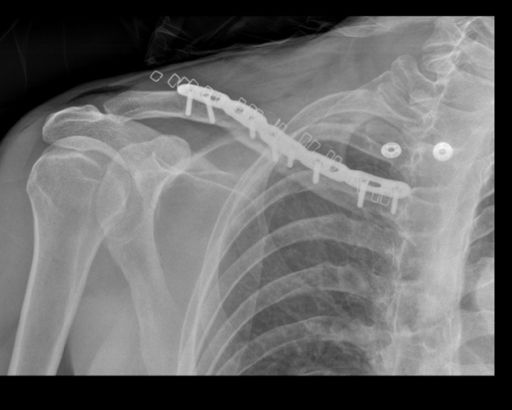

x5 chain-links, x8 screws, x20 staples